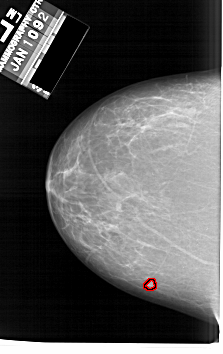

A_1634_1.RIGHT_MLO

RIGHT_MLO LINES 6121 PIXELS_PER_LINE 4006 BITS_PER_PIXEL 12 RESOLUTION 43.5 NON_OVERLAY

FILE: A_1634_1.LEFT_MLO.OVERLAY

TOTAL_ABNORMALITIES 1

ABNORMALITY 1

LESION_TYPE MASS SHAPE LOBULATED MARGINS MICROLOBULATED

ASSESSMENT 4

SUBTLETY 4

PATHOLOGY BENIGN